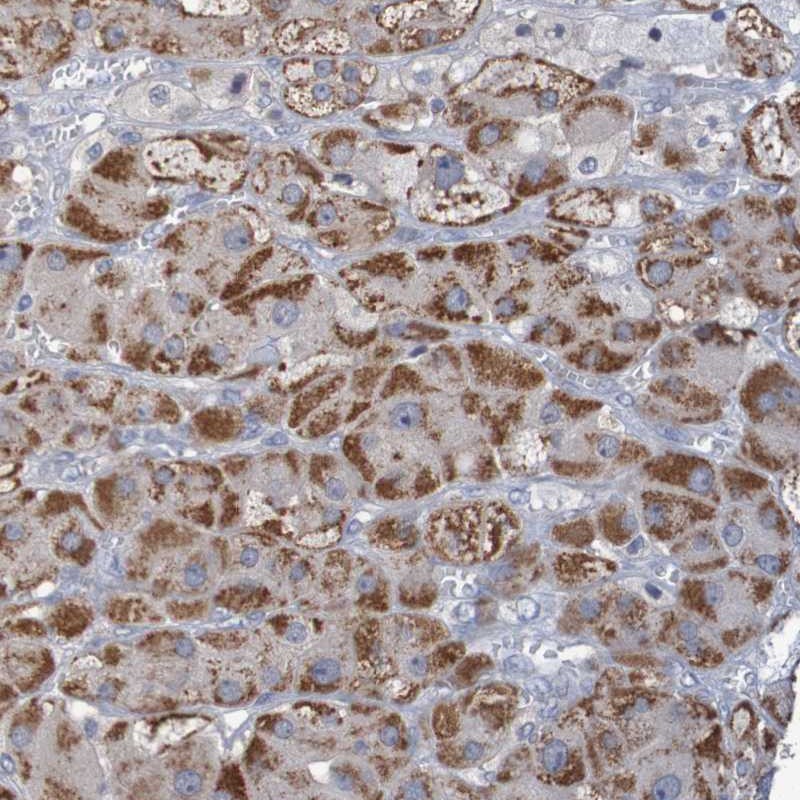

Immunohistochemical staining of human adrenal gland shows strong cytoplasmic positivity in cortical cells.